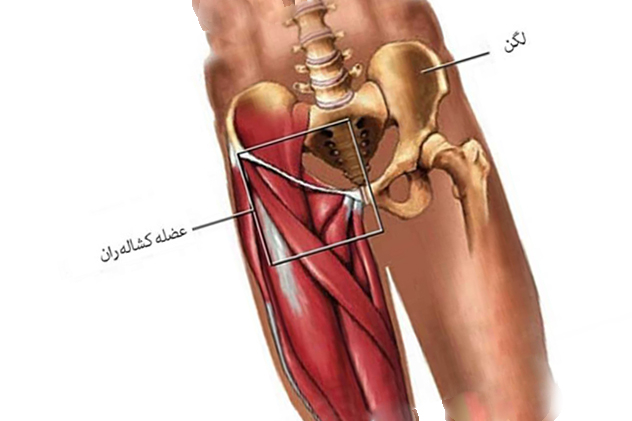

شکل 1 بهترین فیزیوتراپی در اصفهان

قسمت اتصال شکم و ران را کشاله ران می گویند. عوامل زیادی باعث درد در این ناحیه می شوند. بعضی از دردها به راحتی درمان می شوند ولی برخی دیگر نیاز به مراجعه به پزشک و مراقبت بیشتری دارند. به بهترین فیزیوتراپی در اصفهان و دکتر قولنج مراجعه کنید. معمولا درد کشاله ران در ورزشکاران مرد بیشتر شیوع دارد. درد در اثر یک فعالیت ورزشی به یکباره یا به تدریج ایجاد می شود. در این شرایط ورزش مربوطه را نباید ادامه داد.

شکل 1 بهترین فیزیوتراپی در اصفهان

کشیده شدن عضلات

رایج ترین دلایلی که باعث درد در کشاله ران می شود کشیدگی رباط ها، تاندون ها یا عضلات می باشد. در اکثر موارد این نوع کشیدگی ها به راحتی درمان می شود. استراحت، انجام حرکات کششی و داروهای مسکن راه های درمان هستند.